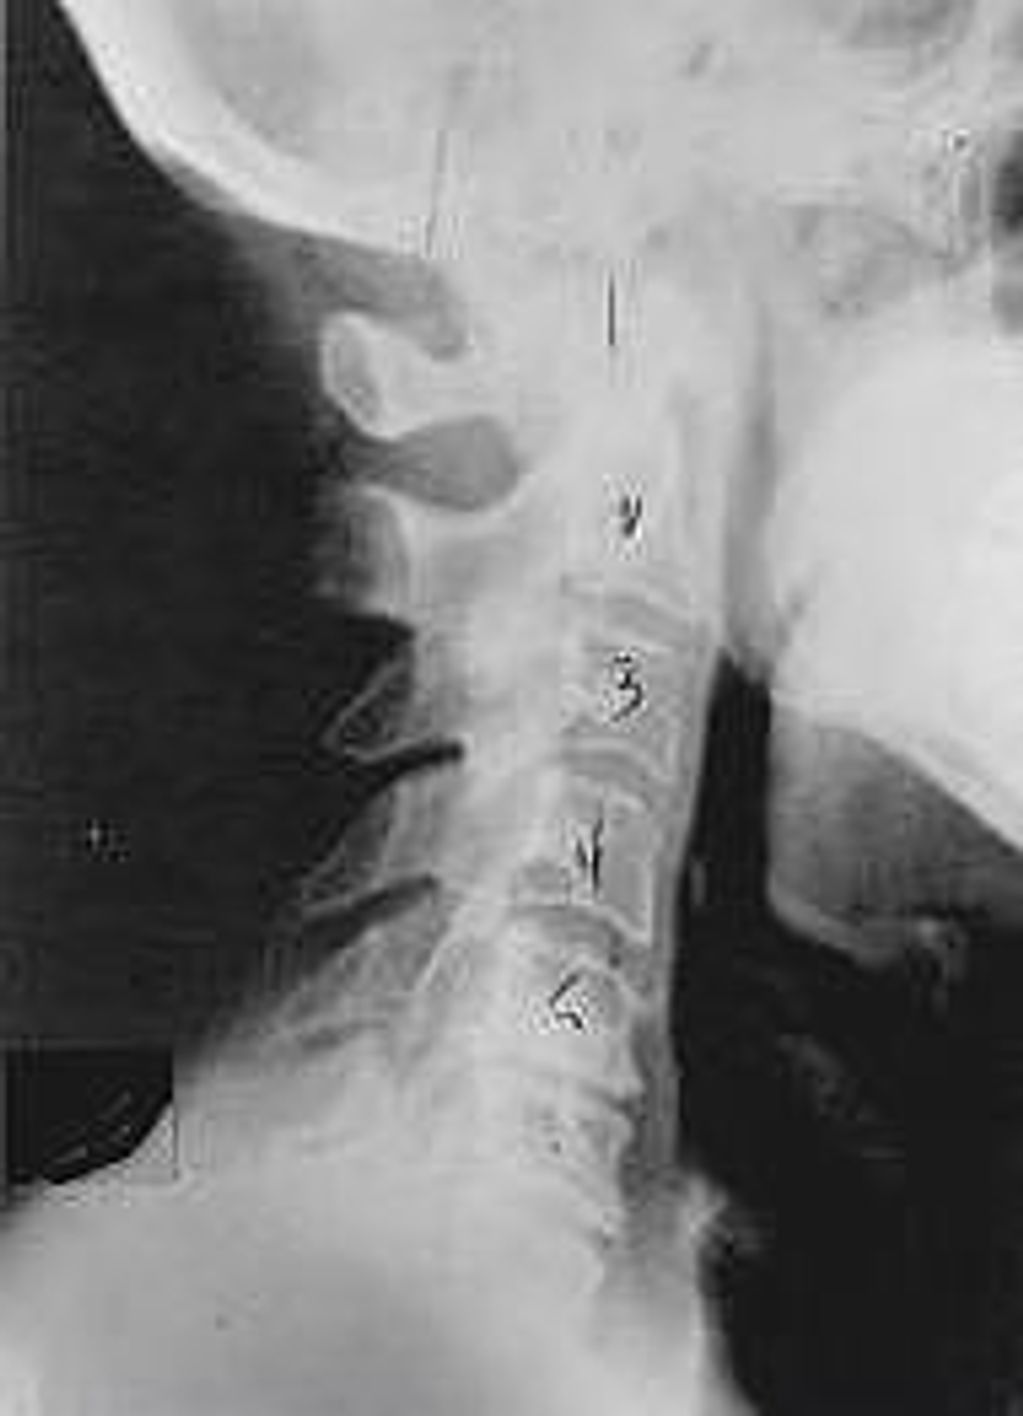

Phase Two Subluxation Degeneration

Phase two subluxation degeneration is normally seen in subluxations that have been present between 20 and 40 years. This phase has some of the same characteristics of the previous phase including a loss of normal curvature and position as well as an alteration in segmental motion. In addition, spines with Phase Two Subluxation Degeneration many times sho